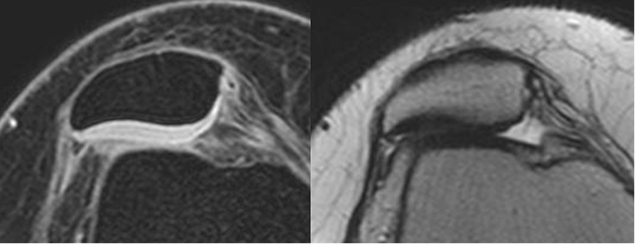

Fig 164. Inestabilidad patelar transversal.

A: RM axial 3D T1 STIR y B: RM axial en T2. Desplazamiento lateral de la patela, sin alteración del cartílago articular.